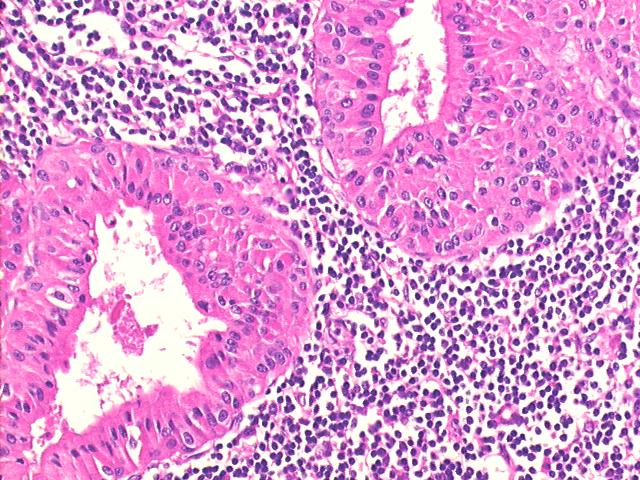

Bilateral parotid nodules, 55-year old male, Warthin“s tumor (adenolymphoma)

Cytologically, the Warthin tumor (adenolymphoma) has a double cell population: lymphocytes and oncocytic epithelial cells that line the cystic areas (sometimes with papillary projections). In the differential diagnosis one should consider the well-differentiated acinic cell carcinoma associated with lymphoid stroma .

All patients with this tumor survive, and the recurrence rate is about 5%. The Warthin tumor tends to be bilateral (10% of cases) and is usually found in the major glands, as seen in the present case.